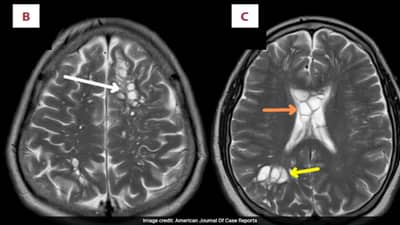

हॉस्पिटलमध्ये जेव्हा या व्यक्तीच्या मेंदूची सोनोग्राफी आणि इतर चाचण्या करण्यात आल्या तेव्हा डॉक्टरांना त्याच्या मेंदू अळ्या सापडल्या. या अळ्या आणि किडे जीवंत होते. या अळ्यांनी त्या व्यक्तीच्या मेंदूत अंडी देखील घातली होती. Tapeworm हा खरेतर परजीवी अळी असून ती वास्तविक आतड्यांमध्ये तयार होऊ शकते. परंतू तिचा मेंदू शिरकाव होण्याचे काही कारण दिसून येईना. तेव्हा डॉक्टरांनी या व्यक्तीच्या मेंदूचा आणि आहाराचा देखील अभ्यास केला. कळले की या अमेरिकन व्यक्तीने अर्धवट कच्चे मांस खाल्याने हे किडे वा अळ्या त्याच्या मेंदूपर्यंत पोहचल्या. ही व्यक्ती लहानपणापासून ( Undercooked Bacon ) बेकन हा पदार्थ खात होता. ही डीश डुकराच्या मांसापासून तयार केली जाते. अर्धवट शिजवलेल्या मांसात अनेक बॅक्टेरिया असतात. जे सेवन करणाऱ्यांच्या आतड्यात जाऊ शकतात. हे किडे आतड्यातून मेंदूत पोहचू शकतात. आणि वेगाने आपली संख्या वाढवू शकतात. आणि मेंदूत अंडी देखील घालतात.

‘अमेरिकन जर्नल ऑफ केस रिपोटर्स’ या घटनेसंबंधीचा रिपोर्ट प्रसिद्ध झाला आहे. अमेरिकेत यापूर्वी देखील संक्रमित पोर्क ( डुक्कर ) ने इन्फेक्शन झाल्याचे प्रकार उघडकीस आले होते. त्यामुळे ही केस सर्वसाधारण आहे. आता या व्यक्तीच्या मेंदूतील अळ्यांचा खात्मा करण्यात आला आहे. आता त्याची मायग्रेनपासून सुटका देखील झाली आहे. अमेरिकन जर्नल ऑफ केस रिपोर्टमध्ये म्हटले आहे की हे इन्फेक्शन धोकादायक असून त्याने प्राणावर देखील बेतू शकते.